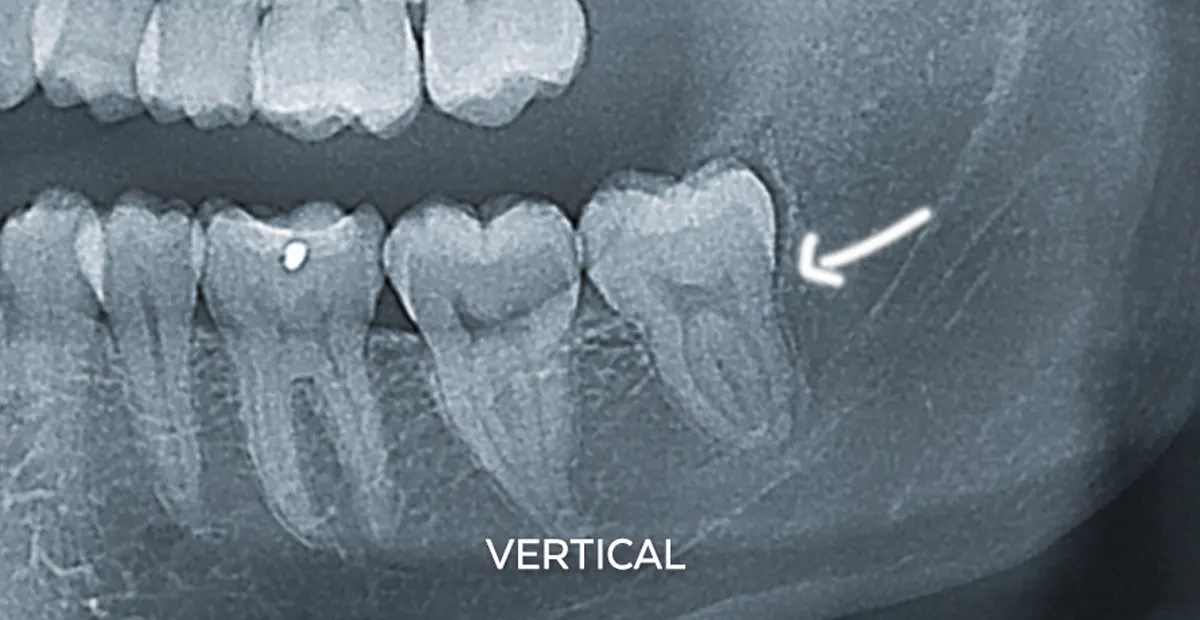

| عمودی (Vertical) | معمولاً بخشی از لثه روی دندان را پوشانده | 🔹 آسان تا متوسط | رایجترین حالت در فضاهای محدود |

به جز معاینه فیزیکی روتین، ممکن است از اشعه ایکس و سایر تکنیک های تصویربرداری، مانند رادیوگرافی پانورامیک، برای تشخیص مشکلات دندان عقل نیز استفاده شود. این تکنیک های تصویربرداری نمای دقیق تری از دندان مولر سوم و موقعیت آنها ارائه می دهند و به دندانپزشک اجازه می دهند متوجه موارد زیر شود:

- نهفته یا نیمه نهفته بودن دندان

- زاویه رشد دندان

- تشخیص آسیب های احتمالی خود دندان

- مشاهده آسیب های وارده به سایر دندان ها و بافت های نگهدارنده از سوی دندان